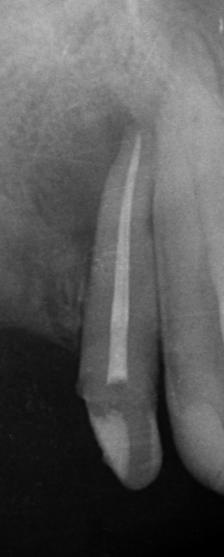

A fenti röntgenképeken egy korábban elhalt, “gócos” fog gyökérkezelés utáni gyógyulásának pillanatképei láthatóak. 1. gyökértömés pillanata 2. négy hónappal később 3. tíz hónnapal a gyökétömés után. Jól kivehető, hogy a gyökércsúcs körüli “fekete folt” fokozatosan “kifehéredik”, azaz a gyulladástól elpusztult csont visszaépül.

Amennyiben a gyökércsatornában lévő baktériumok eltávolításra kerülnek és a csatornarendszert hermetikusan zárjuk, jó esély kínálkozik a szervezet számára, hogy a bacik okozta észrevétlen gyulladás mérete fokozatosan csökkenjen majd megszűnjön. A létrejött csontdefektust 1-2-3 év alatt reparálódik, az elpusztult csont visszaépül.